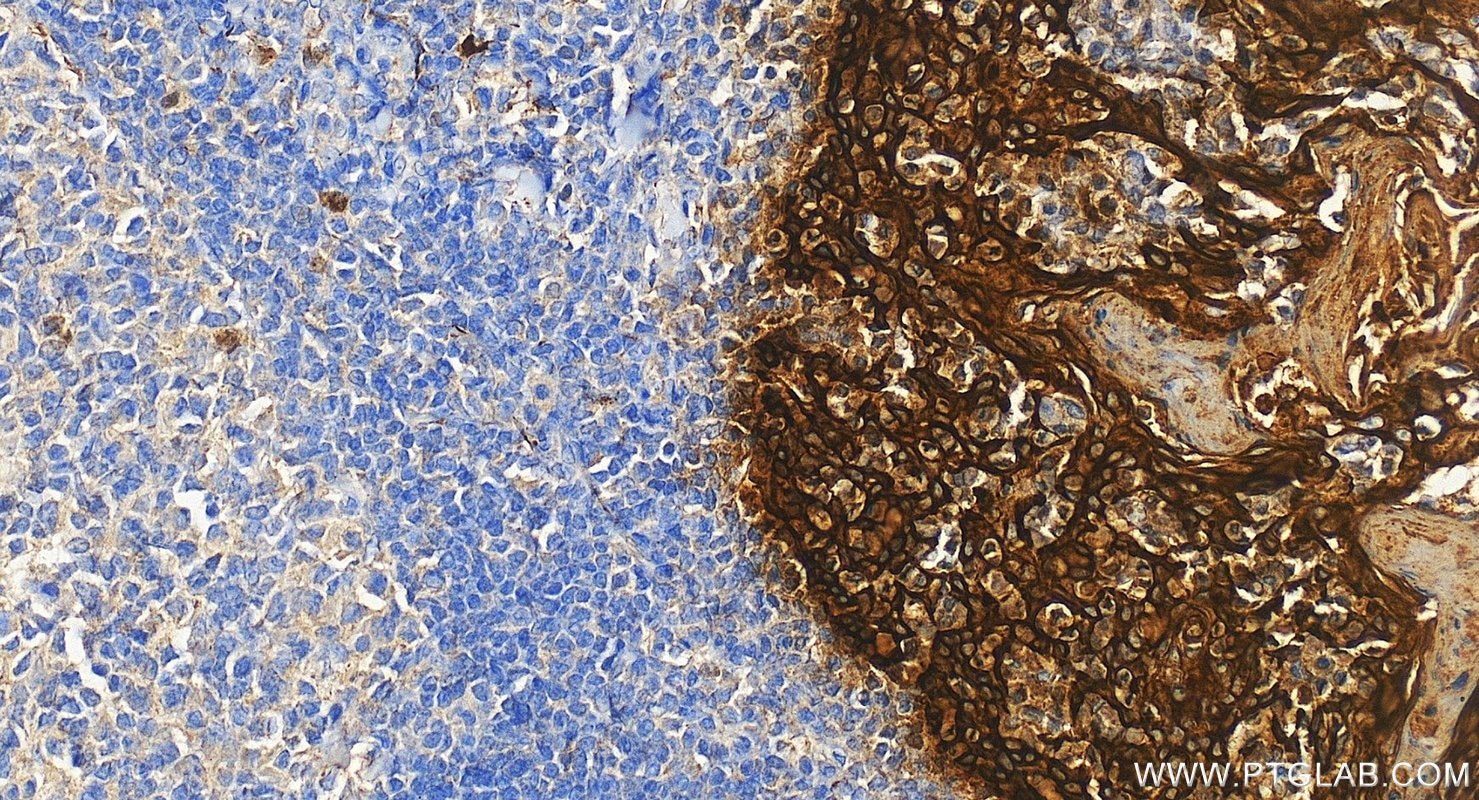

IHC staining of human tonsillitis using 26411-1-AP

Immunohistochemical analysis of paraffin-embedded human tonsillitis tissue slide using 26411-1-AP (Pan-Keratin antibody) at dilution of 1:3000 (under 20x lens). Heat mediated antigen retrieval with Tris-EDTA buffer (pH 9.0).